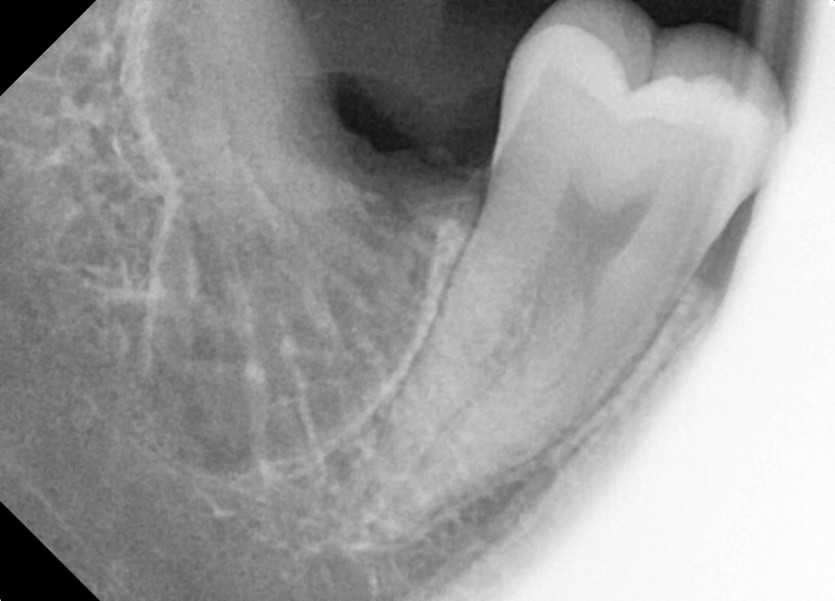

#18,28,38,48 사랑니 발치

구강 외과 전문의가 당일 발치했습니다.